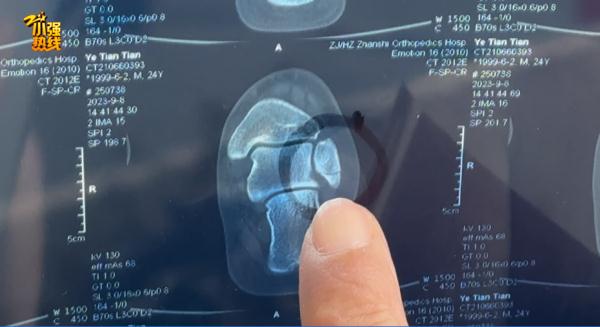

浙江医院三墩院区医务部杨主任回应了此事:“第一次拍的片子是没有明显骨折,但不代表你没有骨折。因为当时轻微的骨折不一定显现得出来,或者说我们的医生不一定能够在你最早的片子上面发现。第一次的片子,现在回过头来看,是可以看出一丝骨折迹象的。但当时我们没有办法通过这个片子,来明确这个地方就是骨折。”

叶先生提供了儿子第一次的X光检查报告,上面显示“无明显骨折征象”。之后儿子回家静养了一个星期,可是脚伤不但没有好转,反而还越来越严重了:“已经肿得很厉害了,第二次来,挂了一个骨科,没有再拍片,医生还是诊断没有骨折,说可能是经脉受伤了,回去安心养伤就是了。”

第二家医院的诊断报告显示,“左外踝骨折、左下肢皮肤感染等”,“患者于9月8号至9月12号住院治疗”。